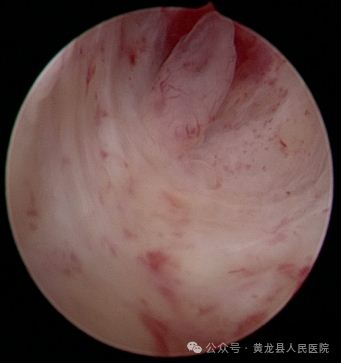

子宫内膜息肉切除术。

患者王某,52岁,围绝经期妇女,以“不规则阴道出血22天”收治入院。入院后完善相关检查后,行宫腔镜检查术,术中见子宫内膜厚,不平整,双侧输卵管开口不可见,予以行诊断性刮宫术后再次置镜检查,子宫内膜平整,术后病检子宫内膜息肉,给予长期管理。

术前宫腔术后宫腔